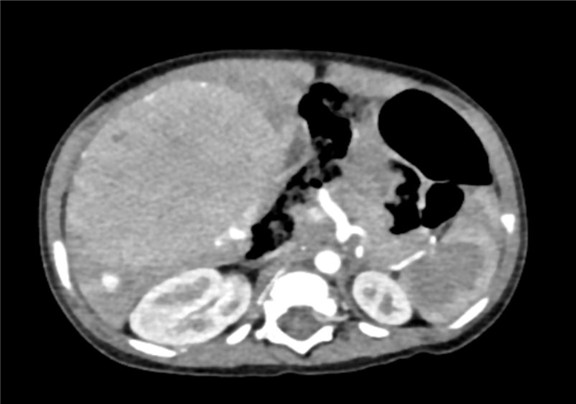

下腹部增强CT示:肝内巨大占位,考虑肝母细胞瘤可能性大,建议MRI平扫+增强进一步检查,腹腔、腹膜后多发肿大淋巴结影,考虑转移瘤可能性大,肝内多发结节,考虑血管瘤可能性大,建议随访

术前CT检查:

动脉期

静脉期